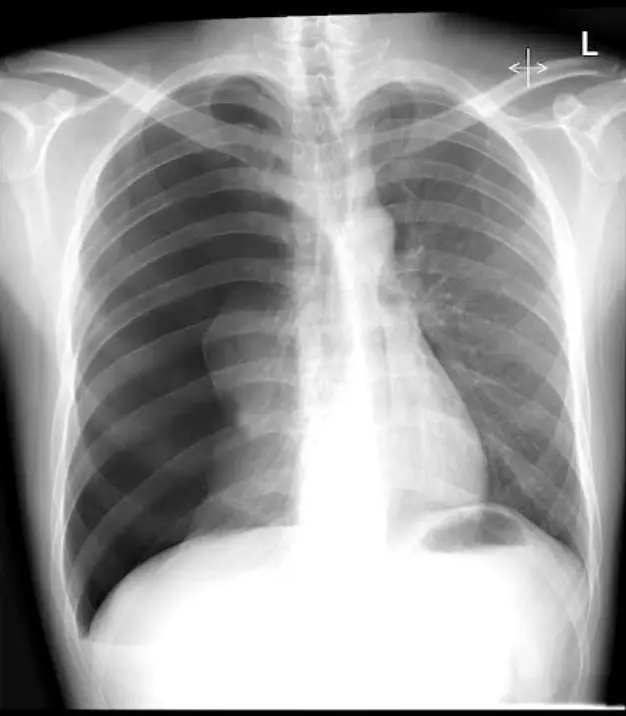

一位25歲男性因呼吸困難至急診就醫,主訴2天前工作撞擊到右側胸部,胸部X光檢查 如圖(三),下列處置何者較適當? 圖片描述

創傷後出現 tension pneumothorax(張力性氣胸)時,首要目標是迅速解除胸腔內正壓、恢復肺部擴張並矯正血流動力學壓迫,因此需立即行「減壓+胸管置入」。影像可見單側高度透亮、肺紋理消失,伴隨縱膈左移與橫膈下降。

從正面胸部 X 光可見:

1. 右側整片肺野呈高度透亮,幾乎無血管紋理,顯示大量自由空氣充斥右胸腔。

2. 右肺實質在肺門周圍可見一條皺縮的肺邊緣,代表肺實質已高度萎縮。

3. 心臟與縱膈向左側偏移,氣管亦被推向左側,提示胸腔內壓力升高造成縱膈位移。

4. 右橫膈明顯較左側低,並呈「deep sulcus sign」輪廓,符合張力性氣胸的典型 X 光表現。 綜合判斷:影像高度支持右側 tension pneumothorax。

依據影像及臨床,病人出現創傷後張力性氣胸,已產生縱膈位移與呼吸窘迫。ABCDE 初期處置強調「任何懷疑張力性氣胸者,不應延遲治療以等待影像」。若現場已有胸管設備,可直接於第 4–5 肋間前腋線置入 28–32 Fr chest tube;如無胸管則先以 14–16G 針於第 2 肋間鎖骨中線做 needle thoracostomy,隨後置管持續引流。選項 A 為唯一符合急救流程之措施。

1. Tension pneumothorax 影像特徵:單側肺透亮、肺紋理消失、縱膈與氣管偏移、橫膈下移或 deep sulcus sign。